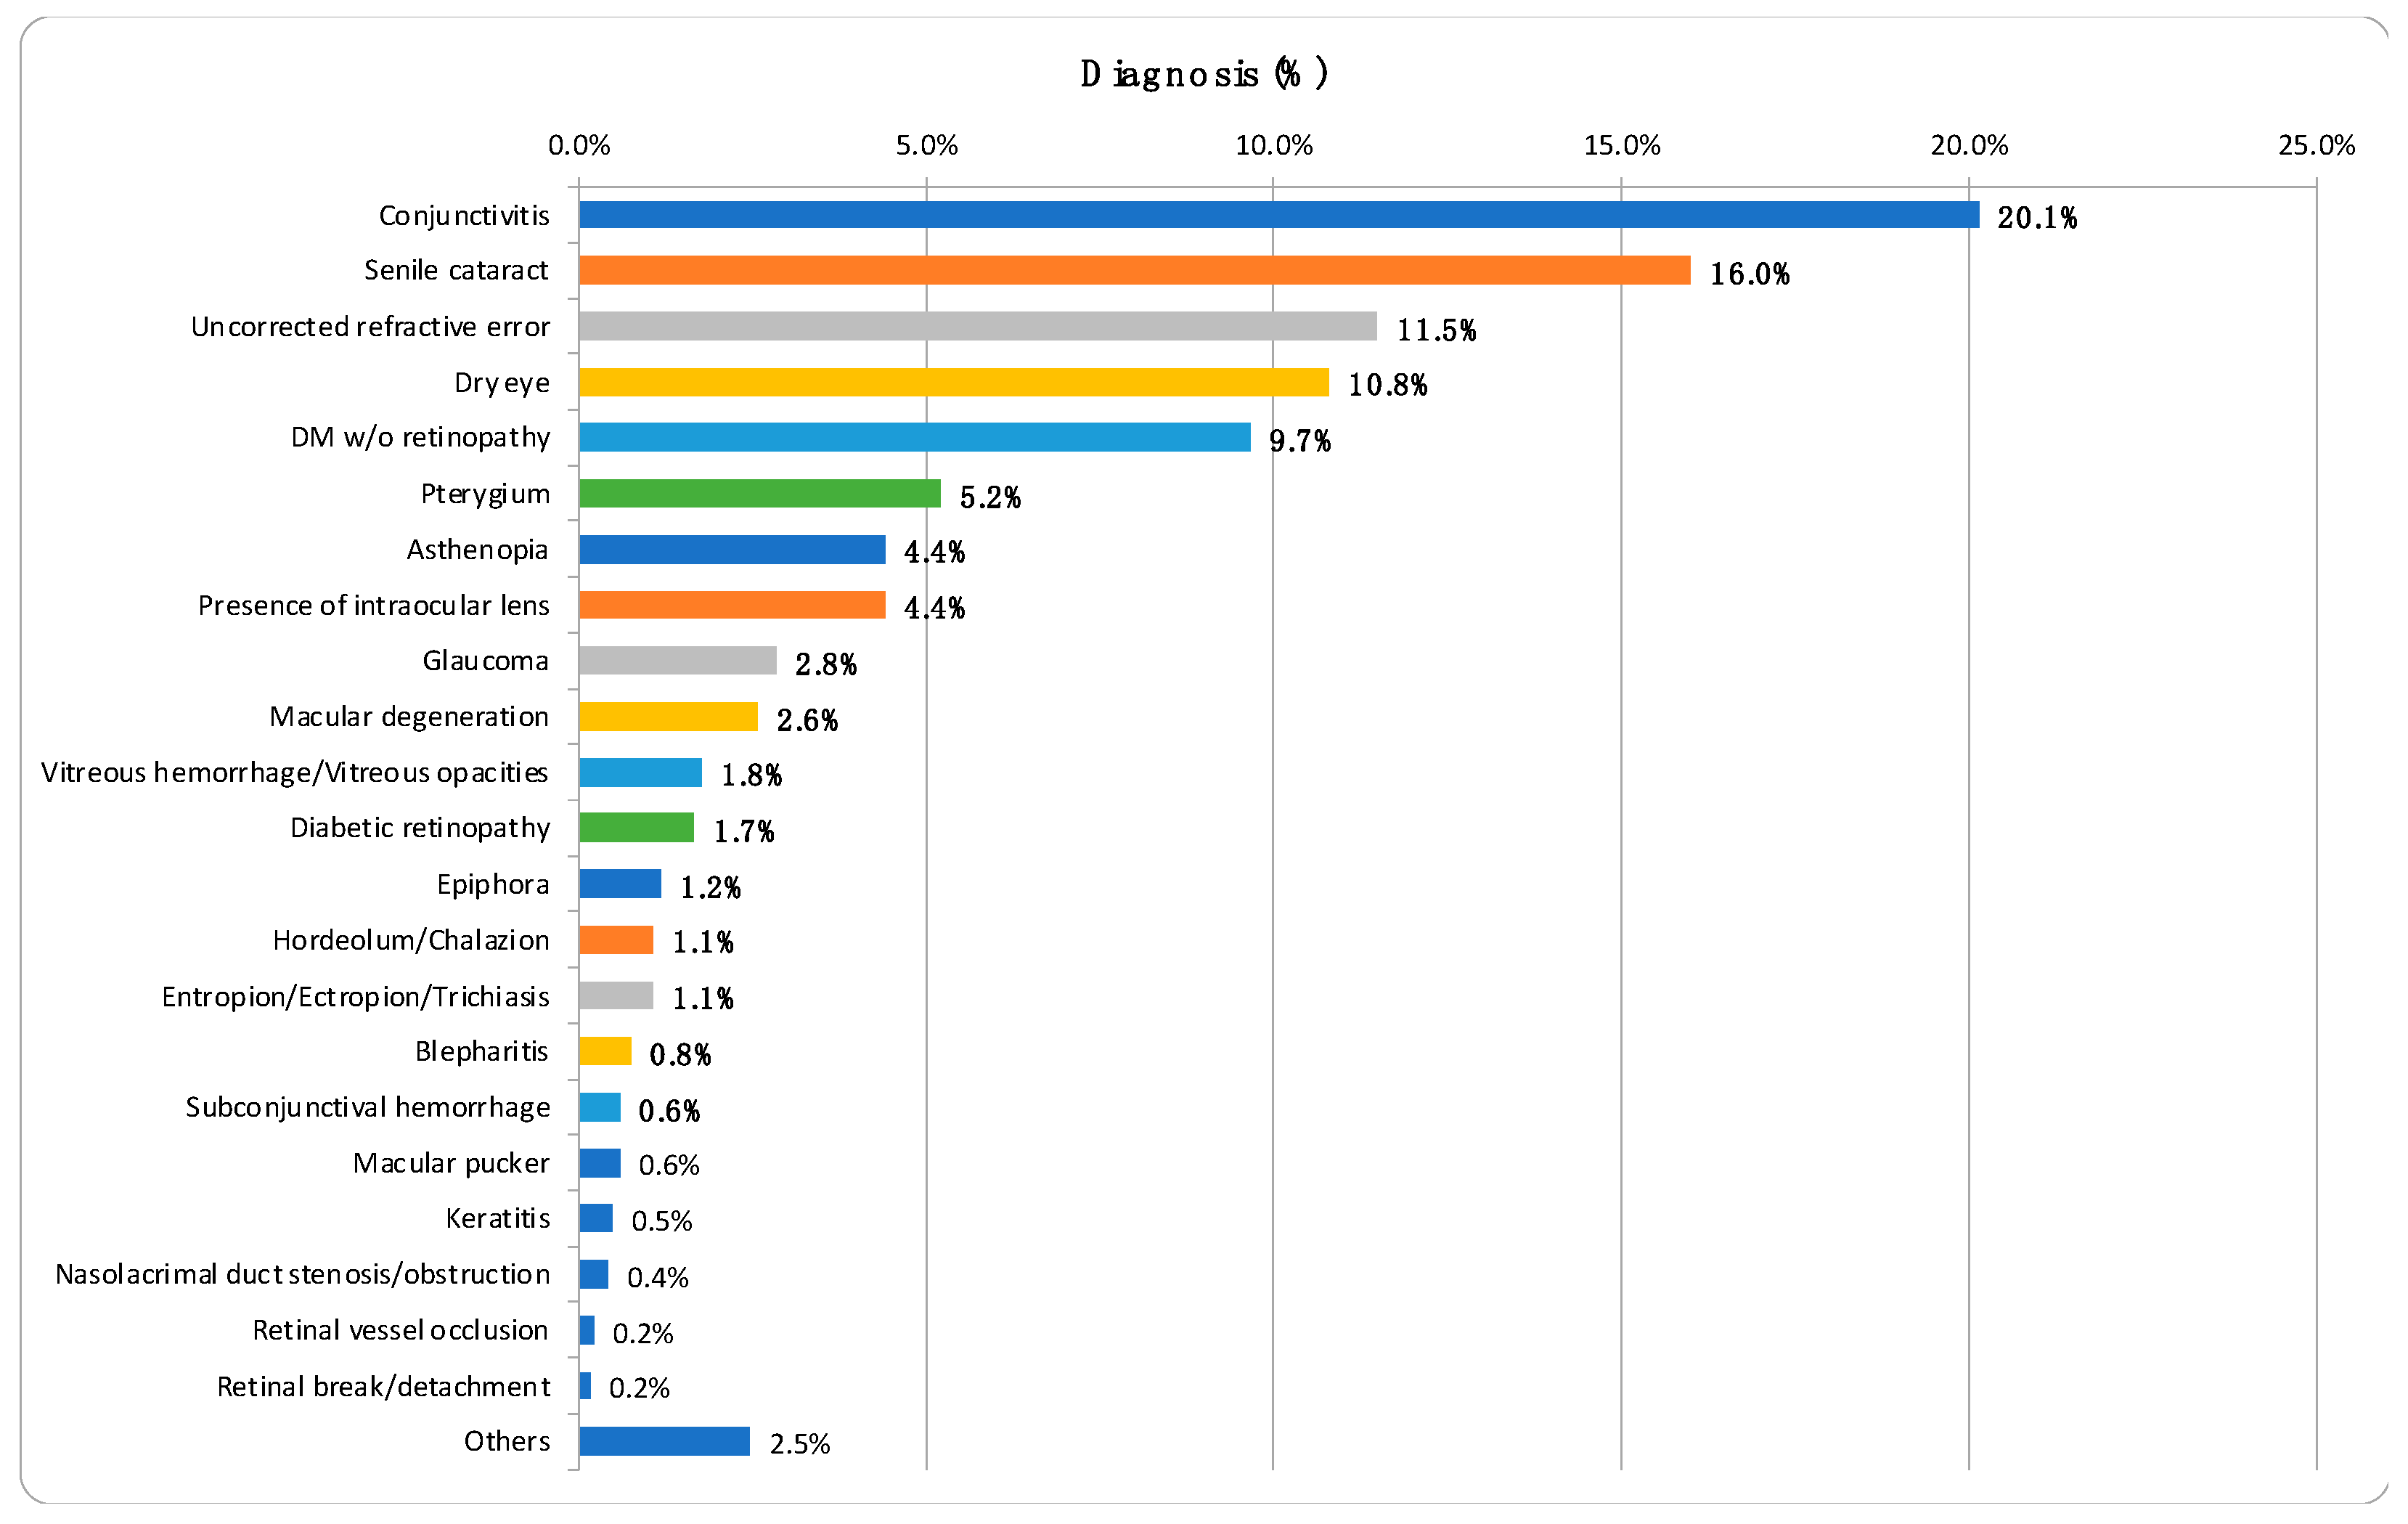

3.2. Distribution of Ocular Diseases

3.3. Evaluation of Fundoscopy Image Quality